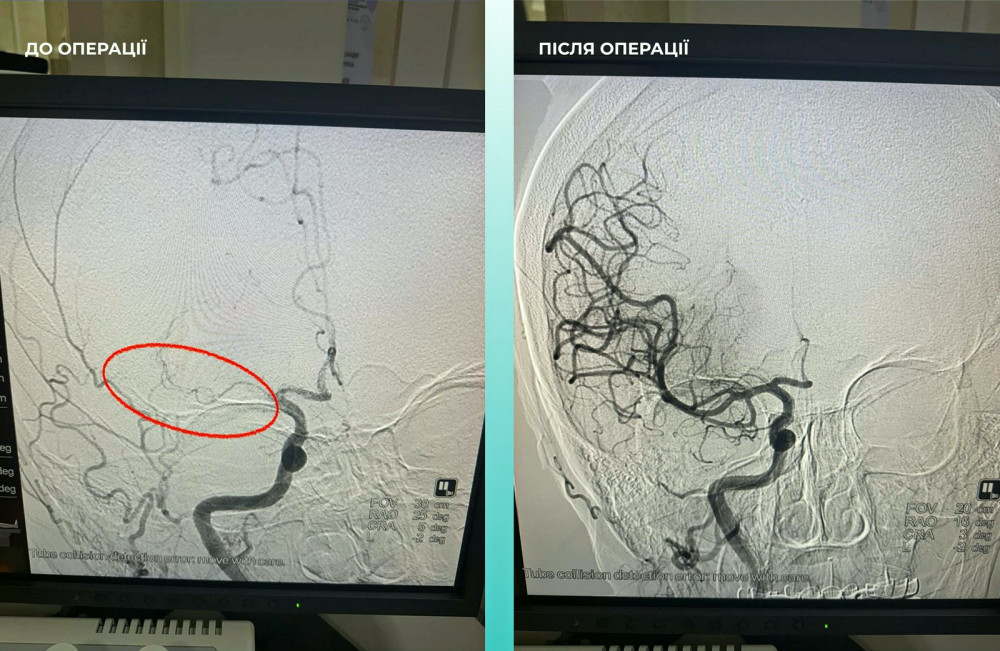

Пацієнтка, одеситка, була госпіталізована з важким гострим мозковим інсультом. Під час комп'ютерної томографії медики виявили закриття середньої мозкової артерії.

Мультидисциплінарна команда спеціалістів прийняла важливе рішення — провести одночасну тромбектомію в мозковій та легеневій артеріях.

Операція пройшла успішно. Наразі пацієнтка почувається значно краще: вона в свідомості та може рухати кінцівками.